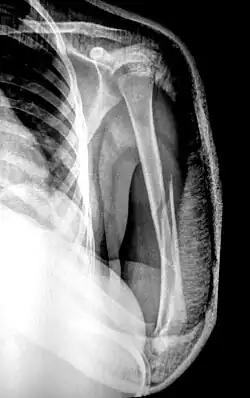

There are two main categories of fracture reductions: closed reductions and open reductions. Both procedures require confirmatory imaging – such as X-ray – both before the reduction to confirm the misalignment of bones and after the reduction procedure to confirm successful achievement of anatomical positioning.

Closed reduction is when bone alignment is achieved from external manipulation of the bone without having to open the skin.[3] This is not a surgical procedure and is often performed in the emergency department with local anesthetic for pain management.[4][5] A distal radial fracture (wrist)[6] is a common injury that requires a closed reduction.

Open reduction is a surgical procedure in which bone alignment is achieved from internal manipulation of the bone when the skin is open.[7] After reduction of the fractured site, it is common that fixed hardware is put in place to maintain anatomical alignment during bone healing; this process is called fixation. While many open reductions require either internal (ORIF) or external fixation (OREF)[7] there are some fractures that, after open reduction, do not require fixation.[8][9][10]